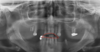

Label the following image:

A

1. red: nasal cavity

2. green: conchae

3. yellow: nasal septum

A: maxillary sinus

B: mandibular canal

C: internal oblique ridge

D: genial tubercle & lingual foramen

E: submandibular fossa

F: zygomatic process

G: nasal septum

H: anterior nasal spine